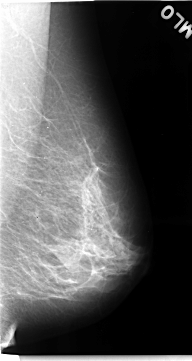

C_0068_1.LEFT_MLO